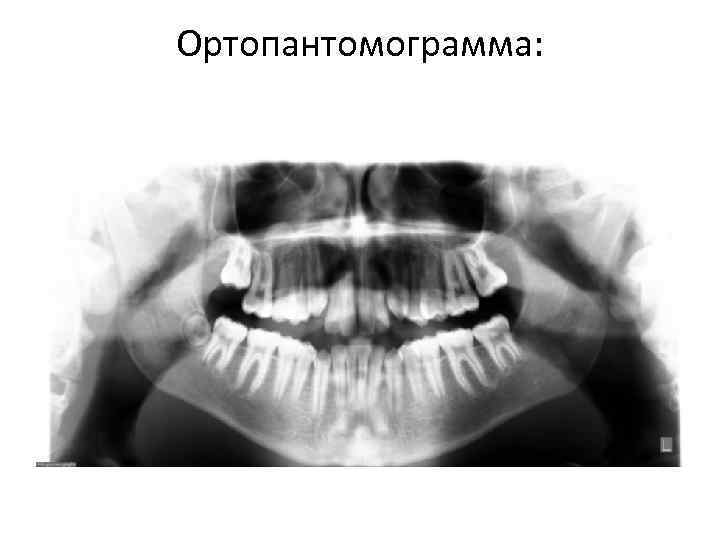

Ортопантомограмма:

Ответ к задаче № 43 • • • 1. Прямой профиль. Недоразвитие средней зоны лица. Мезиальная окклюзия зубных рядов с сужением и укорочением зубных рядов. Обратная и трансверсальная резцовая окклюзия. Двусторонняя перекрестная окклюзия (палатиноокклюзия). Смещение линии косметического центра верхнего зубного ряда вправо на ширину нижнего центрального резца. Мезиальное смещение верхних премоляров и моляров справа. Отсутствие места для 1. 3, супраокклюзионное тортоаномалийное прорезывание. Тортоаномалия 1. 2, 2. 4, 3. 2. Адентия нижних первых постоянных премоляров. 2. Индекс Тонна 32: 23=1, 39 (непропорциональность размеров резцов). Сужение и укорочение зубных рядов (верхнего на 4, 5 мм, 5, 0 мм, 2, 0 мм; нижнего на 3, 5 мм, 4, 0 мм, 2, 0 мм). 3. На ОПТГ: ретенция 1. 3; адентия 3. 4 и 4. 4; смещение линии косметического центра верхнего зубного ряда вправо. На ТРГ: верхняя ретрогнатия, нижняя прогнатия, отрицательный увеличенный межапикальный угол, ретроинклинация нижней челюсти, увеличен базальный угол. Протрузия верхних резцов, ретрузия нижних резцов, увеличен межрезцовый угол.